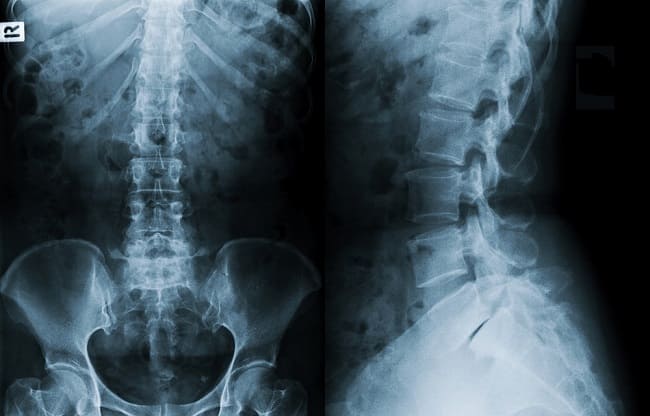

Rontgen tulang belakang digunakan untuk memberi gambaran struktur tulang belakang pada berbagai kasus medis, seperti kecurigaan fraktur, degenerasi diskus, osteoporosis, dan spondilolistesis. Rontgen tulang belakang dapat dilakukan pada berbagai posisi dan letak, dengan mempertimbangkan indikasi klinis.

Rontgen tulang belakang diindikasikan pada kasus trauma, infeksi, deformitas, dan osteoporosis tulang belakang. Rontgen tulang belakang berlangsung cepat dan tidak invasif, sehingga secara umum cocok digunakan sebagai pemeriksaan diagnostik awal.

Terdapat 3 jenis rontgen tulang belakang, yaitu C-spine untuk regio servikal, T-spine untuk torakal, dan L-spine untuk lumbal. [1,2]